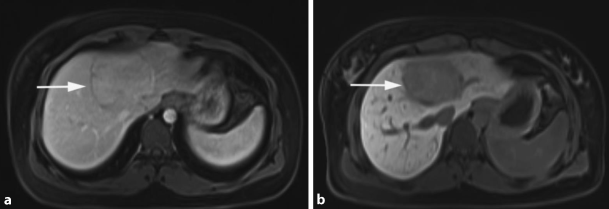

Liver haemangiomas are common incidental findings, reflecting a high prevalence within the common population ranging from 1 to 20% [7]. Originating from the mesodermal layer, these lesions represent a congenital non-neoplastic hamartomatous proliferation of vascular endothelial cells. Macroscopically, these tumours are well-circumscribed hypervascular lesions with good compressibility; hence, no classical evidence for malignant potential is given. The majority of haemangiomas are of the cavernous type, representing the most common BLT. These lesions have been reported in up to 7% in autopsy studies [10]. Unlike the less common capillary-type haemangiomas, which are generally smaller in size, multiple and most commonly asymptomatic cavernous haemangiomas can grow to a large size and may become symptomatic. Giant haemangiomas are defined as those measuring ≥5 cm, while hypergiant hepatic haemangiomas are defined as those which are larger than 10 cm in size [11]. These lesions are more frequent in women (female:male ratio = 5:1), with a mean age at diagnosis of 50 years [12]. The certainty of diagnosis sustained by high-quality non-invasive imaging represents still an important step. Transabdominal ultrasound (US) is diagnostic in approximately two thirds of cases [13]. However, axial imaging may be undertaken and is crucial prior to therapy. Haemangiomas tend to be hypodense on native computed tomography and show centripetal contrast uptake. These characteristics are of important value in differentiating haemangiomas from metastases [14]. Magnetic resonance imaging (MRI) may also be of importance in difficult cases. As shown in Fig. 1, typical features include high signal intensity on T2-weighted series and discontinuous nodular peripheral enhancement. Diagnostic biopsy to differentiate giant haemangiomas from malignant lesions should in general be discouraged. On the one hand there is a reported risk of haemorrhage of up to 0.28% [15], on the other hand the risk of needle track seeding and intra-abdominal dissemination of a potentially curable malignancy is of clinical importance [10]. Cavernous haemangiomas occur more frequently in the right liver, an association with oral contraceptives (OCPs) still remains controversial [10]. Current evidence reveals an uncomplicated natural history of these lesions.

Fig. 1

Haemangioma in segment V: axial T2-weighted (a), arterial phase (b) and late phase approximately 2 min after the i. v. injection of contrast agent (c). Typical hyperintense signal in the T2-weighted images and the peripheral enhancement in the arterial phase with nearly isointense presentation in the late phase